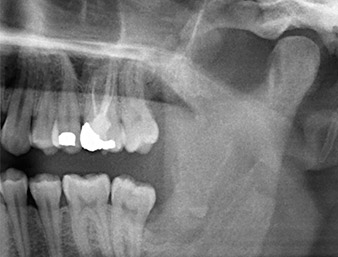

A 26-year old patient complained of constant pain and paraesthesia after surgical removal of a retained wisdom tooth. Panoramic radiographs confirmed a root remnant located in close proximity to the inferior alveolar nerve.

The root remnant in the region of tooth 38 (LL8) was already displaying close proximity to the inferior alveolar nerve on the OPG. The root had fractured during the osteotomy but had not been removed by the primary treatment provider due to intraoperative pain. To ensure as little trauma as possible to the tissue, the new osteotomy was to be carried out using a piezo surgical system. The patient had an unremarkable medical history and was a non-smoker.

It could be seen in the 3D image (digital volume tomography) that the root remnant was located disto-caudally in the transition from the horizontal to the ascending portion of the mandible (Fig. 2).